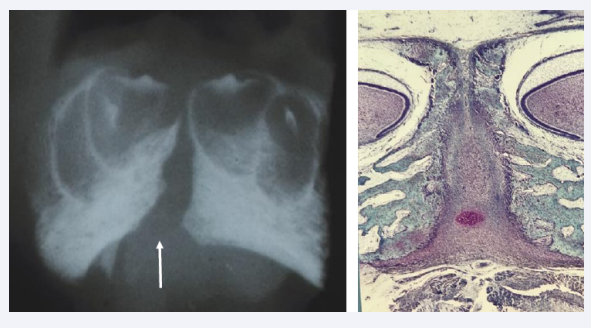

Figure 7 Left: Frontal radiograph of the mental region in a human fetus19 weeks of Gestation. The radiograph taken with a bone sensitive x-ray  machine demonstrates the Symphysis Menti (arrow) and bony alveolae for the primary incisors, where dentine and enamel formation have  started. Right: Frontal histological section of the specimen demonstrated in the left figure. The broad Symphysis menti is registered, richly vascularized,  and bordered by bilateral bone tissue with tooth buds located in alveoli.

Figure 7: Left: Frontal radiograph of the mental region in a human fetus19 weeks of Gestation. The radiograph taken with a bone sensitive x-ray machine demonstrates the Symphysis Menti (arrow) and bony alveolae for the primary incisors, where dentine and enamel formation have started. Right: Frontal histological section of the specimen demonstrated in the left figure. The broad Symphysis menti is registered, richly vascularized, and bordered by bilateral bone tissue with tooth buds located in alveoli.